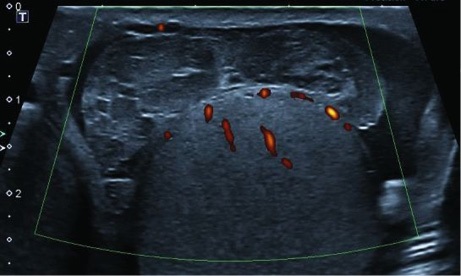

Характерными ультразвуковыми симптомами явились (см. рис. 1):

- гематома позади яичка при сохранении/нарушении целостности его белочной оболочки;

- неоднородность структуры придатка при малом сроке травмы, исключающем развитие посттравматического эпидидимита;

- явное нарушение контура придатка.

Рис. 1. А. Неоднородность структуры придатка с участками «выпадения» кровотока в нём на фоне сохранённого тестикулярного кровотока